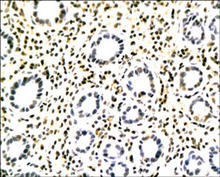

实验图片 :

TLR2 (CD282) staining in rat stomach. Paraffin-embedded rat stomach is stained with TLR2 Antibody (Cat. No. 251110) used at 1:200 dilution.                   The TLR2 Antibody (Cat. No. 251110) is used in Western blot to detect TLR2 in rat lung lysates.